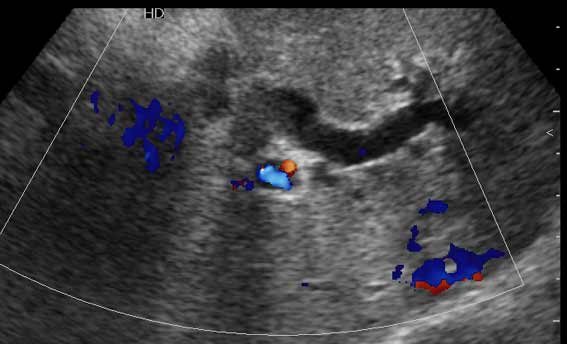

Очень пожилая женщина, обратилась в стационар из-за появления желтухи. Периодически беспокоили боли в эпигастрии и правом подреберье.

Желчный пузырь удален по поводу ЖКБ лет двадцать назад.

Не могу сказать что я вижу камень в холедохе на представленных сонограммах. Холедох расширен; интра-печёночные жёлчные пути тоже (значит прошло > 3 недель от момента обструкции). Жалоб на сильные приступообразные боли я не прочёл. Всё таки буду думать сначала о опухоли (если при УЗИ не нашли камня); рекомендация-таргетное КТ печени и поджелудочной.

Дело в том, что в холедохе имеется нечто изоэхогенное (не знаю, видно ли это нечто на ваших мониторах). Врач УЗИ при осмотре перед поступлением в стационар на основании этой картины в заключении отметил возможность опухоли холедоха.

Гнойный холангит на фоне обструкции БДС конкрементом (камень вне скана). В холедохе определяется желчь с осадком, которая может быть ошибочно принята за его опухоль.